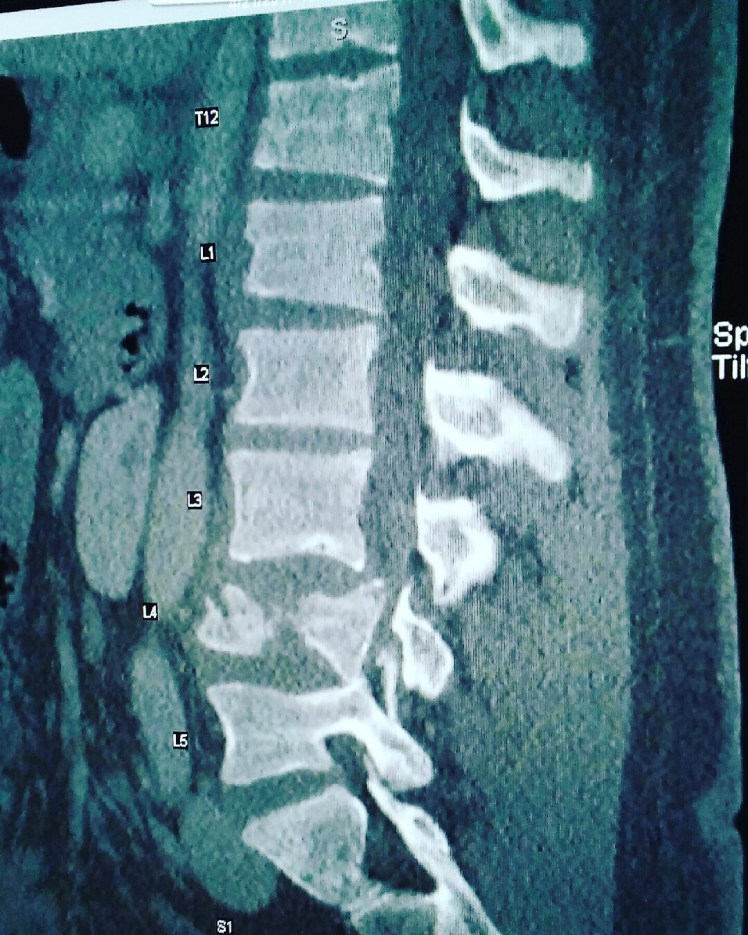

I spent eight days in KMC. Two days after the fall I had surgery. They got me in there, flipped me over and split my back open. I got eight screws and two rods. My ankle also had a hairline fracture.

So I had one 7-hour surgery. I burst fractured my L4, which required eight titanium screws and two titanium rods.

The day after my surgery, the neurosurgeon came in and said “Good news! Successful surgery and we also fixed your scoliosis.” I was like, “what are you talking about I don’t have scoliosis.” Apparently, if I had not fallen, I would have had the same surgery 10 years from now to fix whatever scoliosis I had.